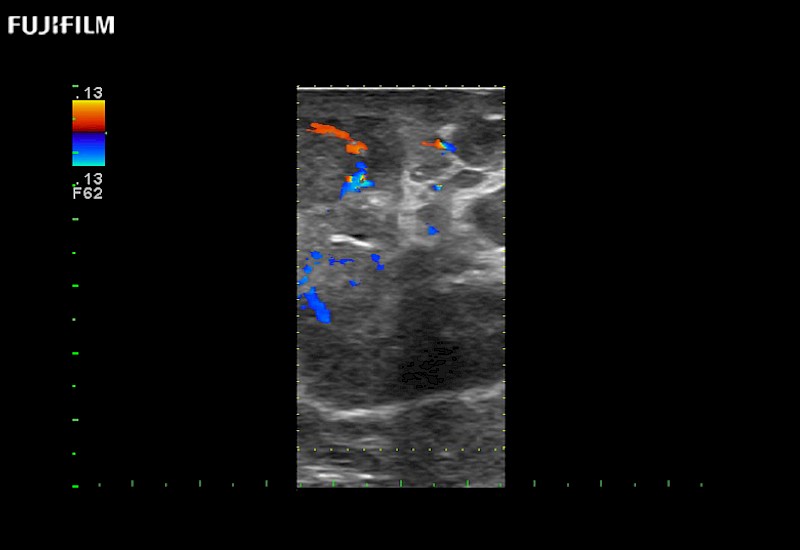

Learn moreFujifilm Healthcare continues to listen to the experts, our neurosurgeons, by developing an ultrasound system specifically designed for the Operating Room.

Guidance is the fundamental purpose for all of our surgical ultrasound technology. Fujifilm Healthcare is committed to designing tools that help neurosurgeons navigate inside the human body and provide the necessary information to immediately make critical surgical decisions.

With the ARIETTA Precision the next level of surgical ultrasound is here.